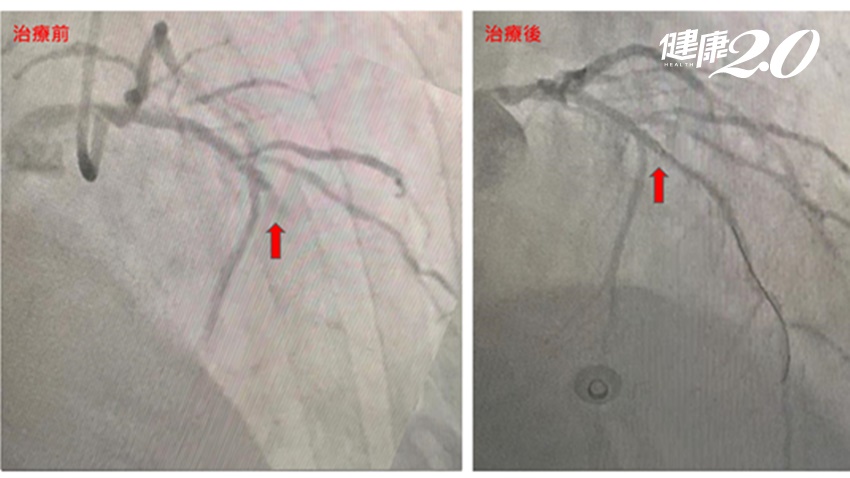

洪惠風解釋,現在認為,血管剛開始出現變化,「是血管壁愈來愈厚」。當血管壁愈來愈厚,剛開始對內徑不太有影響。但到最後有的人就會向內擠壓,影響血管內徑,產生心絞痛症狀。但也有人沒經過這個階段,在血管壁變很厚時,沒向內擠壓,就粥塊破裂,產生血栓,血栓把血管完全堵塞,就是心肌梗塞。一旦堵住這個點之後,後方的肌肉得不到血流供應就會壞死,稱為「心肌梗塞」。